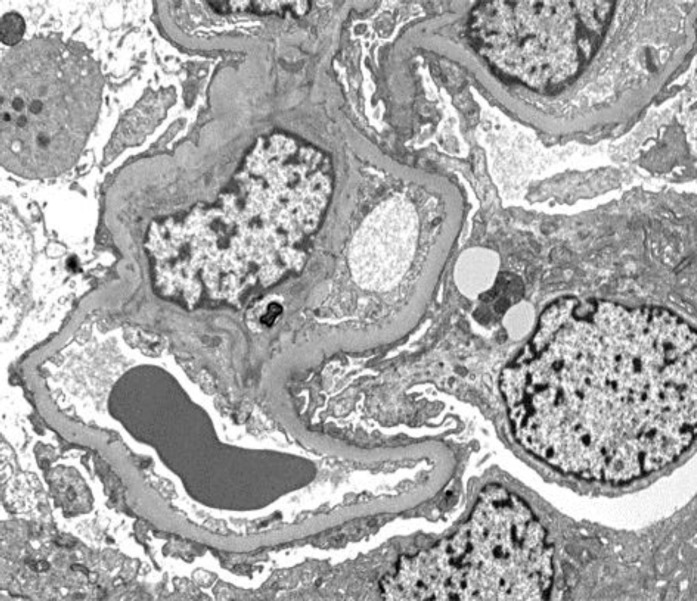

Background: We describe the case of a young woman with seasonal allergic rhinitis who presented with signs of a lower respiratory tract infection, acute renal impairment and the nephrotic syndrome, demonstrated on biopsy to be due to minimal change disease (MCD) with acute tubular injury. Following initiation of high-dose corticosteroids, her respiratory symptoms and renal impairment improved, and the nephrotic syndrome went rapidly into remission, but relapsed, off treatment, in a seasonal fashion.

Management: In view of significant side effects related to corticosteroids, relapses were treated with the calcineurin inhibitor tacrolimus with excellent effect, but the patient was keen to avoid the complications of medium-term immunosuppression and so the drug was weaned early. She relapsed for the second time, whilst off tacrolimus, at the same time of year as at her initial presentation. In subsequent years we have successfully managed this patient with seasonal relapsing MCD with seasonal prophylactic tacrolimus therapy.

Discussion: We discuss the natural history of MCD and treatment options and demonstrate the utility of a clear understanding of the natural history of the condition in order to predict disease relapse and tailor therapy to the individual patient.